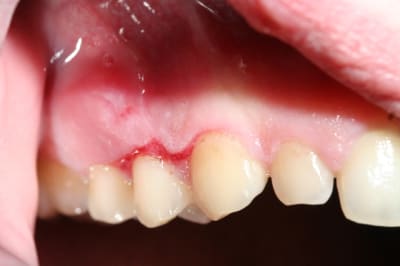

désolé de venir encore perturber votre post mais je voudrais profiter de vos compétences.

patiente vue cet après-midi :

27 ans

grande période de stress

l'état d'ulcération de la gencive ne semble pas passer malgré la reprise du brossage.

D'emblée je pense pas à un truc de malade mais plutôt à des traumatismes locaux faits par le patiente lui-même avec une brosse à dent toute pourrie avec des poils pliés et des problèmes d'hygiène de départ suite à fatigue ou soirée alcoolisée ou les muqueuses sont parfois très fragiles.

Est-ce possible d'après toi qui connait la personne ?

Conclusion = quelque chose de bénin, 1 semaine de bain de bouche et réévaluation

brossage régulier en constante amélioration depuis deux semaines

brosse à dent Inava Parodontie neuve (c'est pas une brosse chir mais c'est pas la plus dure non plus)

prescription de piasclédine depuis un mois

bains de bouche quotidiens

certes l'état général de la gencive est beaucoup mieux mais je ne m'explique pas cette disposition symétrique des ulcérations et le fait que cela ne semble pas vouloir disparaitre.

Pr Dentiste 57 je repond comme Canin (encore une fois) meme si les lesions ont l'air symetriques et qu'en generale il y a tjrs un coté ou on s'acharne plus, en secteur 1 sur la gencive adherent y'a comme un dérapage de brosse a dent .

pas d'ATCD ?

pas de médoc ?

pas d'autre lésions ?

Tartre ? car ont dirait un truc commme ca sur 16 ?

si alcool a gogo il peut aussi avoir deficience vitaminique ?

Si clope et alcool et stress on peut envisager un debut de GUNA meme si cela n'en a pas l'air pr l'instant.

clope et stress: OK

alcool , je ne pense pas : cette patiente est saine

elle m'a dit être très fatigué et prendre depuis 1 mois des compléments vitaminiques.

pour la GUN je ne trouve pas que cela y ressemble

BOn ben ce qu'on sait

jeune 27 ans

stress

tabac

dure depuis au moins 2 semaines

(pas de grossesse ?, post partum ?)

- GUN mais c'est pas un aspect typique

- Neutropénie cyclique mais en générale c'est connue depuis longtps(Les manifestations commencent au cours de la deuxième enfance., ça s'en va et ca reviens dixit Claude Francois.

ma collaboratrice a eu ma patiente en consultation, gencive purulente, papilles légèrement décapitées.

alors c'est bien une GUN non ?